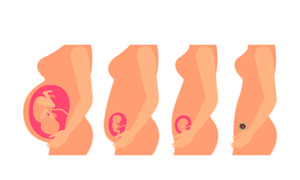

很多人在避孕的时候会选择结扎手术,这是一种通过对女性的输卵管进行手术的避孕方式,避孕的效果还是比较有效的。但是,国家二胎致使很多的家庭想要备孕二胎,对于结扎过的家庭来说也是有想法的,那么结过扎能人工受孕吗?

孕24周产检项目有哪些?众所周知,怀孕24周时需要去做一次产检,但是极少有人了解孕24粥产检项目的内容,尤其是新妈妈。今天我们就来了解下孕24粥产检项目,看它对准妈妈有多重要!

怀孕期间是非常重要的,特别是怀孕中期,这段时间胎儿正是生长的时候,我们必须要非常注意胎儿的情况。那孕中期产检项目及最佳检查时间你都了解清楚了吗,产检是一定要做的,这能知道胎儿和孕妇的一些情况。那孕中期什么时候检查好呢,要检查些什么呢?

进入孕晚期,宝宝就快要出生,这个时候身体就会出现很多的不适,这就需要孕妇随时关注自己的身体了,要定期做孕晚期产检。孕晚期产检能够检测到胎儿的发育情况,孕妇的羊水情况以及为胎儿的生产做判断,这是非常重要的,大家一定要慎重。